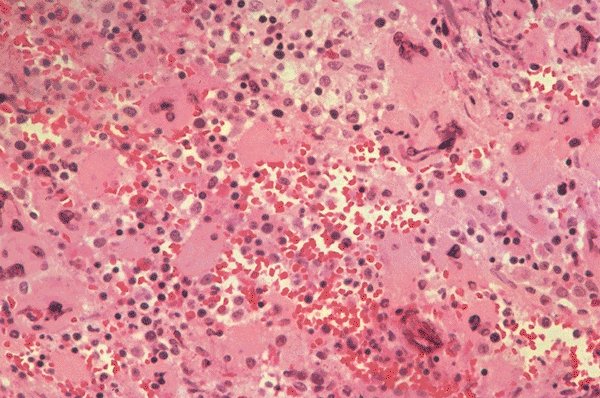

Polycythemia vera

This bone marrow biopsy is seen at very low

power and shows the marked cellularity and

modest fibrosis in a patient with polycythemia

vera. Multiple megakaryocytes are also seen.